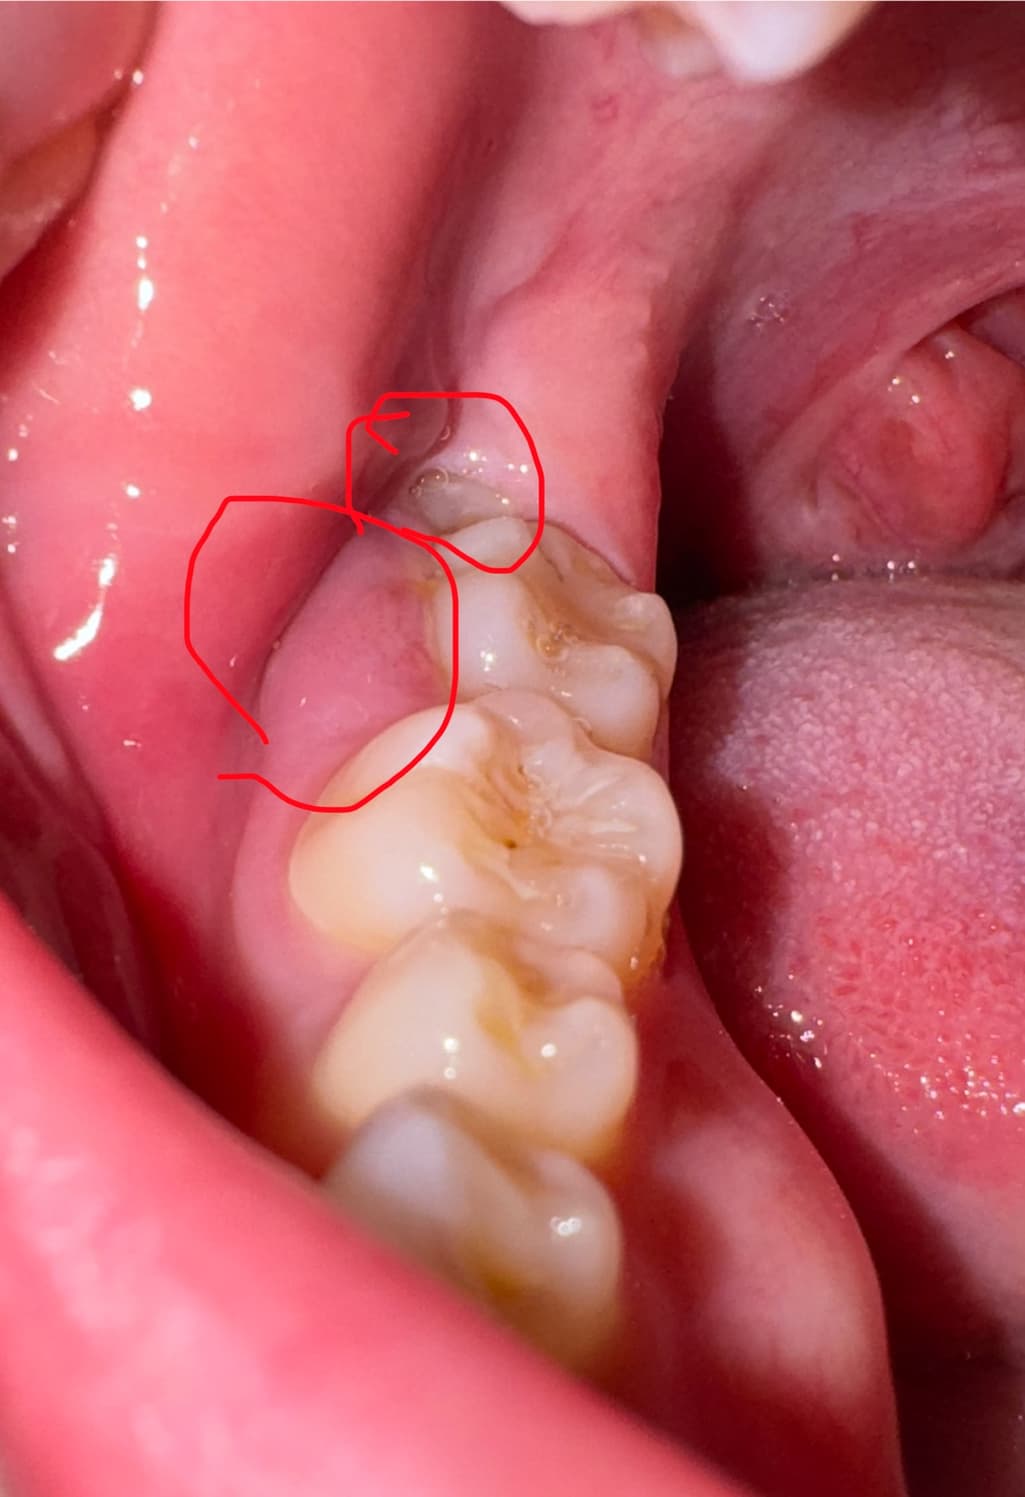

사랑니가 누워서 자란 것 같은데 갑자기 오른쪽이 아파서 사랑니발치하러 다음주 금요일 10일에 예약을 한 상태인데 사진과 같은 상황입니다!ㅠㅠ사랑니가 조금 보이고 주위 잇몸이 부었어요ㅠㅠ음식 씹을때 아파서 왼쪽으로만 씹고있어요 긴 연휴라서 병원도 못가는데 심각한 상황일까요?? 일주일 뒤에 병원가도 안 늦을까요??

사랑니로 인해서 염증이 생겼을 수도 있고 단순히 잇몸에 염증 물질로 인해서 염증이 생겼을 수 있습니다. 사진으로 봤을 때는 굉장히 급하게 염증이 커진걸로 보여 빠른 치료가 필요할 것으로 생각됩니다.